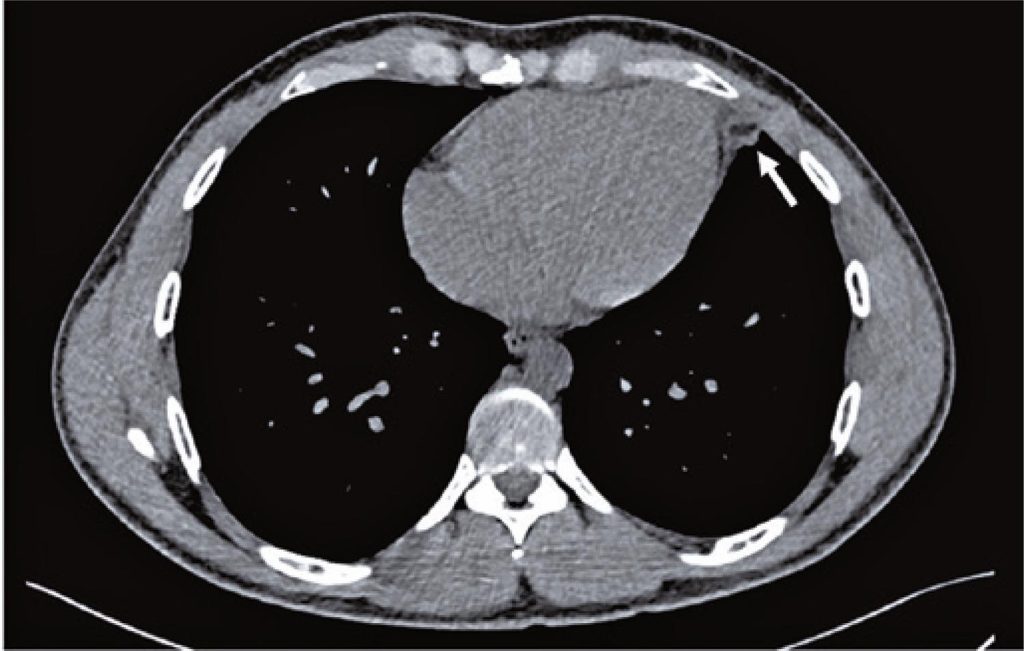

Chest pain is a frequent, potentially life-threatening condition in the emergency department and requires immediate investigation and treatment. This case report highlights a rare differential diagnosis of pleuritic chest pain: epipericardial fat necrosis. A 29-year-old man presented with normal clinical evaluation, electrocardiography, point-of-care ultrasound, and unremarkable laboratory tests. The initial hypothesis was acute pleuritis. Chest radiography revealed peri-cardiac nonspecific findings, and computed tomography revealed epicardial fat necrosis. Despite the rarity of this condition, accurate diagnosis allows for better practices. An algorithm for a diagnostic approach is proposed.